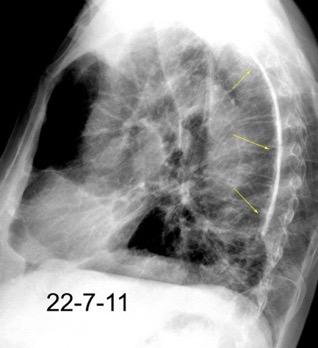

Neumonía a neumococos base izda. con derrame que aumenta.

Broncograma en lateral y en US.

(36-66% en ingresados)

66 pacientes con

Tb pleural probada

Ocasionalmente nivel hidro-aéreo por fístula broncopleural Consolidación........3% Ganglios……….....39%

Derrame...................65-98.5%

Lesiones pleurales. ........38 %

Afect. cisura interlobar….9%

Pl. mediastínica........... 1.5%

Afect. pulmonar 26/66 … 39%

Cambios fibróticos..........17%

Cavitación ......................12%

Nódulos heterogéneos.....6%